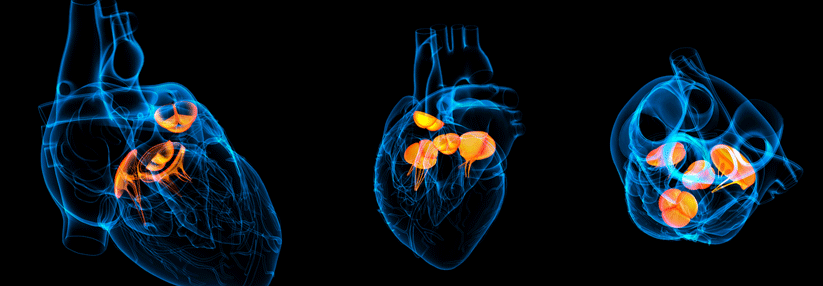

Durch das rheumatische Fieber

kann es zum Beispiel zu einer Stenose

der Mitralklappe kommen. Durch das rheumatische Fieber kann es zum Beispiel zu einer Stenose der Mitralklappe kommen. © iStock.com/ChaNaWiT; wikimedia/CDC